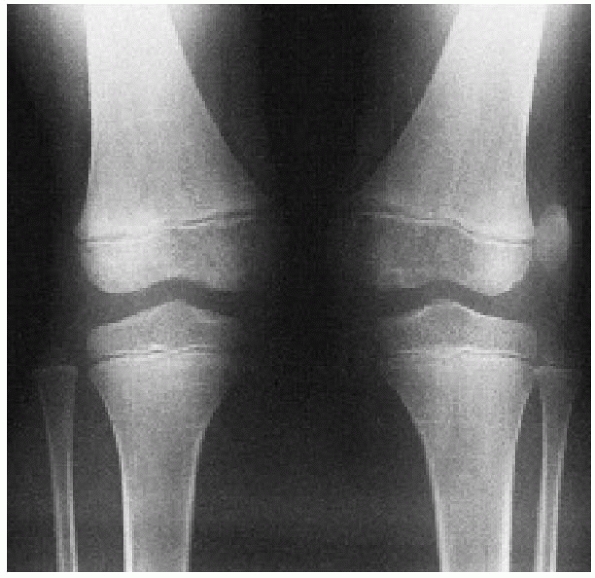

are more common than once thought. They are typically associated with

acute lateral patellar dislocations. The most common locations for

these fractures are the medial patellar facet or the lateral femoral

condyle (Fig. 24-13). The osteochondral

osteochondral fractures associated with acute patella dislocation

ranges from 25% to 50%.13,43,95,206,229,282 Matelic et al.206 found 67% of children presenting with an acute hemarthrosis of the knee had an osteochondral fracture.

should begin with anteroposterior, lateral, and skyline plain

radiographs. However, a roentgenographic diagnosis can be difficult

because even a large osteochondral fragment may contain only a small

ossified portion that is visible on plain radiographs. A tunnel view

may help locate a fragment in the region of the intercondylar notch.

Because the osteochondral fragment may be difficult to see on plain

radiographs, radiographs must be carefully assessed for even the

smallest ossified fragment (Fig. 24-15).